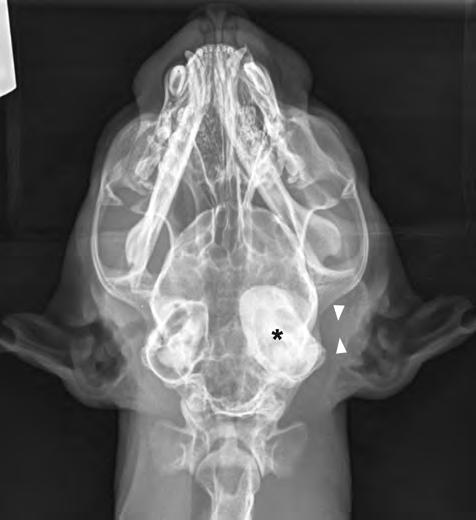

1. Radiografías de la cabeza de un gato maine coon de un año de edad. (A) Proyección lateral. (B) Proyección dorsoventral. (C) Rostro 10º ventrodorsocaudal oblicua.

En la exploración otológica se visualizó una masa en el conducto auditivo externo izquierdo, apreciable desde la abertura del pabellón auricular. La masa era sólida, poco móvil y obstruía totalmente el canal auditivo. El resto del examen físico y pruebas de enfermedades víricas fueron normales. En el análisis sanguíneo se evidenció neutrofilia con desviación a la izquierda y trombocitosis.